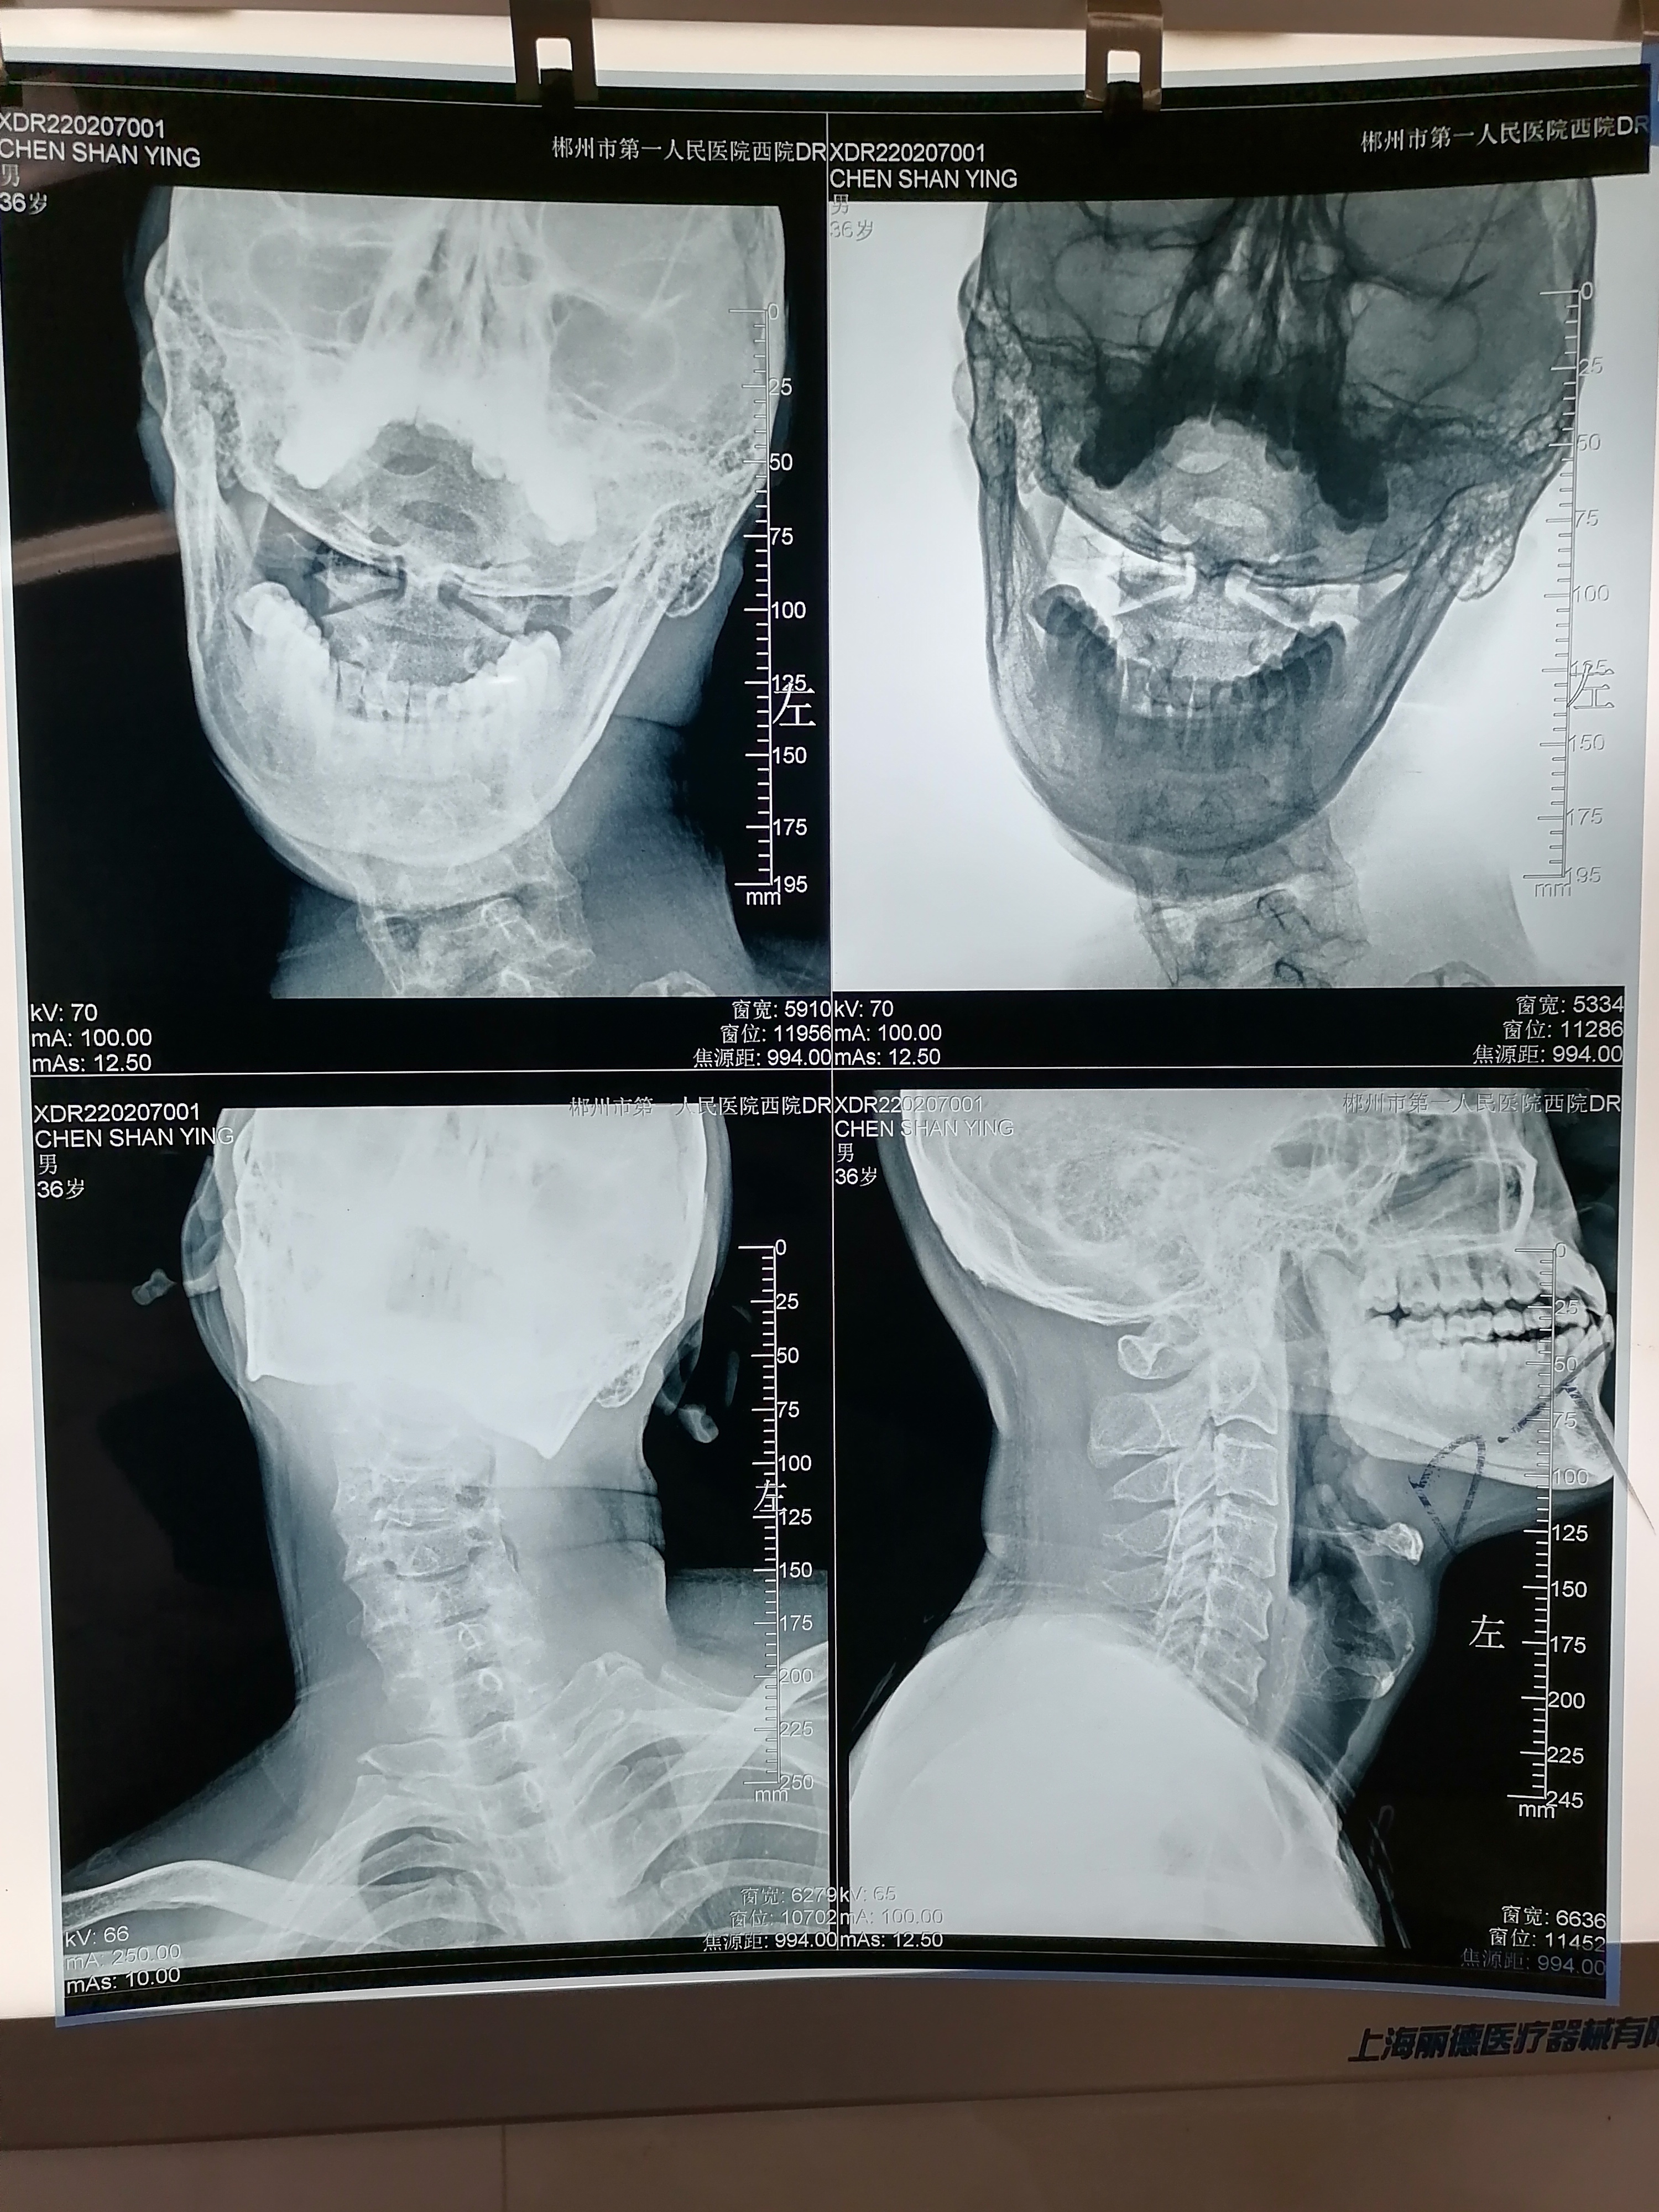

完善相关检查,颈椎X线片示:“右侧环齿关节间隙变窄”积极予以针灸、推拿、药物(乙哌立松)处理,疼痛缓解。本以为就这样没事了,继续他的公交司机生活,继续他的“扭脖子”事业。可半月后颈部疼痛加重,并逐渐出现颈部乏力感,并逐渐左偏,头部右偏困难。患者回到乐昌市某医院就诊,予以手法复位后间断好转,但头部左偏逐渐加重,并且伴随颈椎呈现右侧凸。患者曾到多家医院就诊均予以对症处理后症状稍好转,但反复复发。为求得更好的系统诊治,于是来到了我院康复医学科就诊。

(颈椎张口位片)